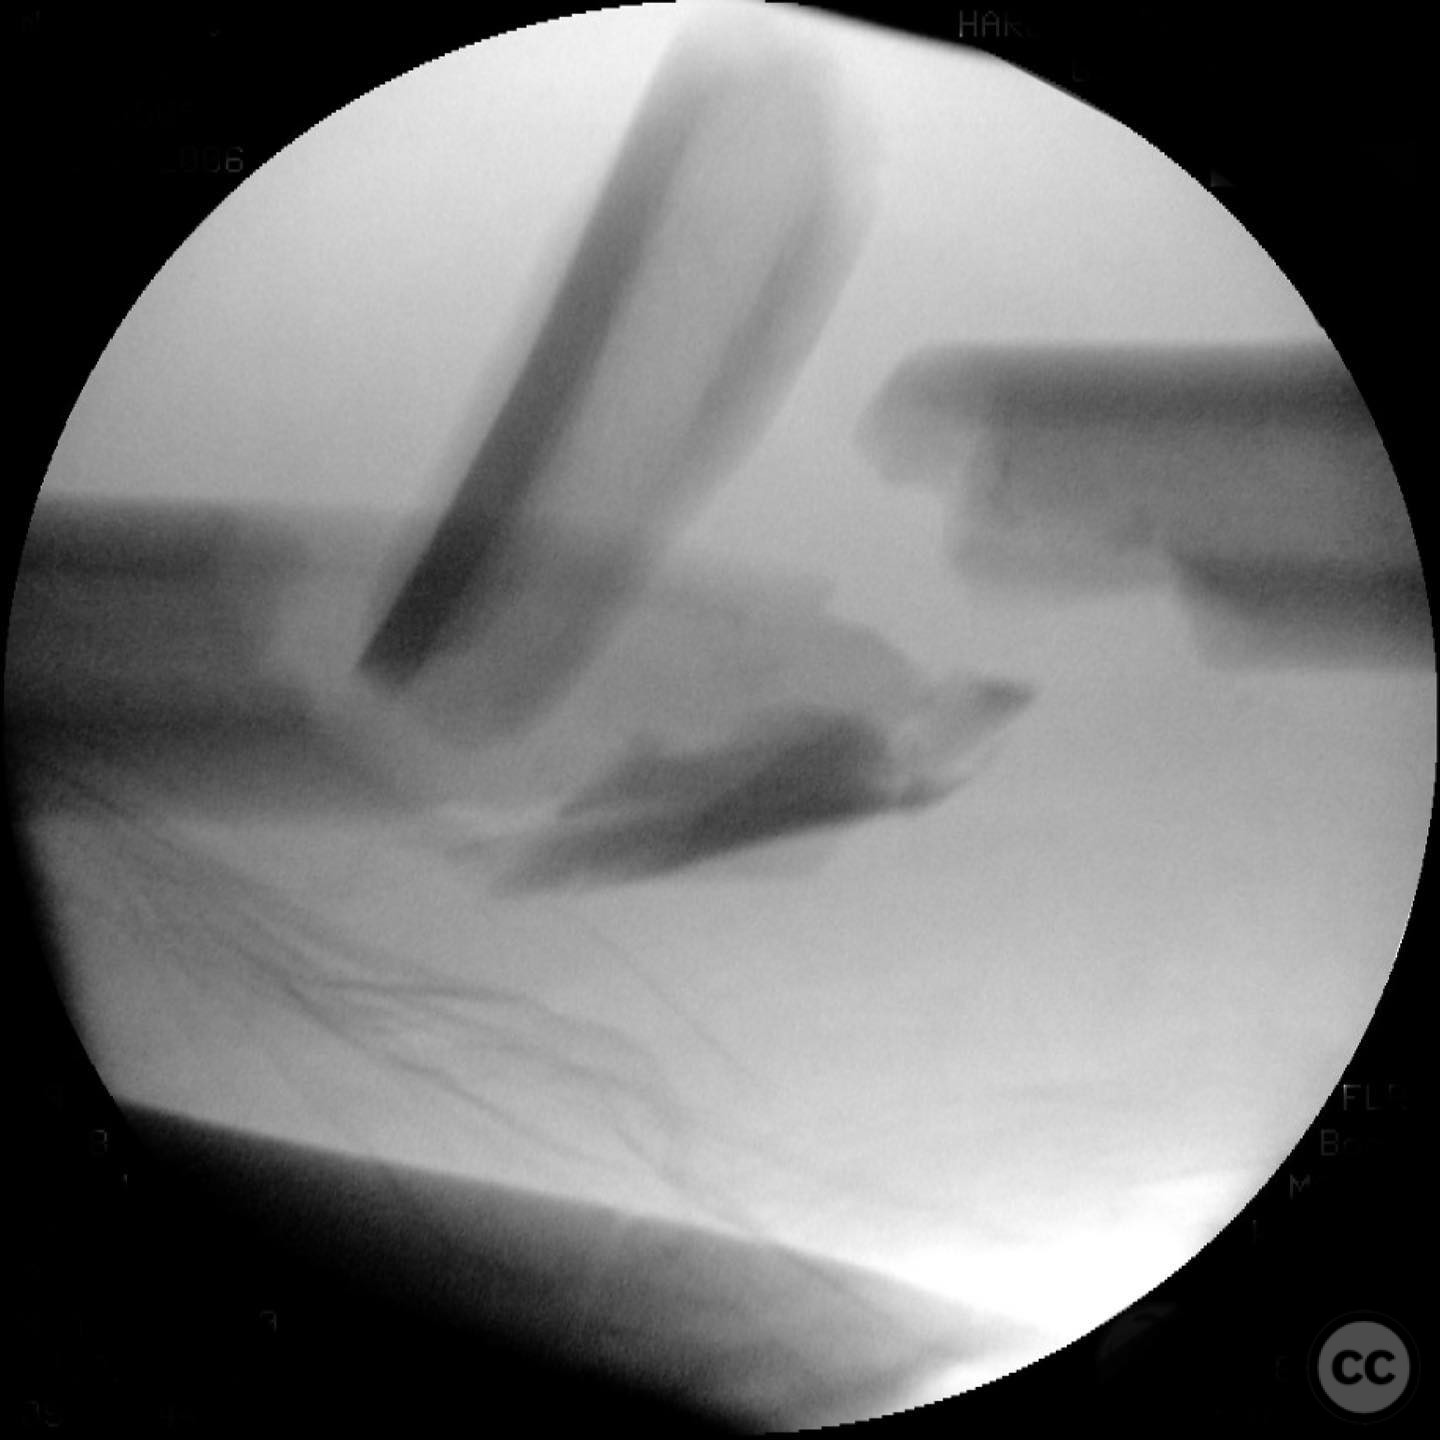

Anatomical surgical approach:  A lateral approach to the femur was performed, involving an incision along the lateral aspect of the thigh. Subperiosteal dissection was carried out to expose the fracture site while preserving as much periosteum as possible. Care was taken not to disturb the medullary hematoma, and reamings were collected for later use in grafting.

Operative remarks:

The surgeon noted that indirect reduction techniques were inadequate due to the fracture's complexity, necessitating an open reduction. Emphasis was placed on preserving fracture biology by minimizing periosteal stripping and avoiding suctioning of the medullary hematoma. Reamings were used as autograft material around the fracture site to enhance healing.